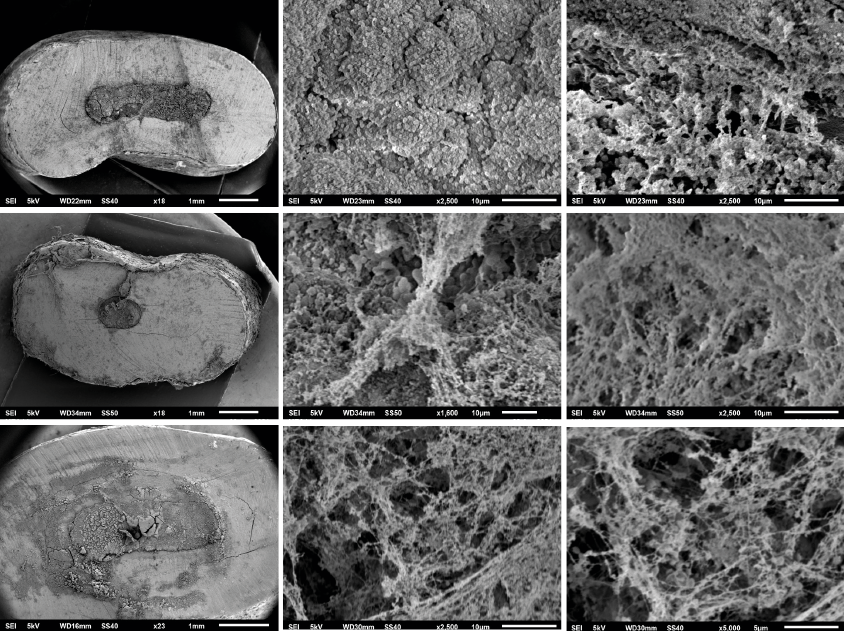

In SEM images was observed that all samples in the experimental groups (Groups 1, 2, 3) showed a rough and irregular surface due to microorganism colonization and biofilm formation, in which could be observed coccoid forms compatibles with E. faecalis, the coccoid forms were found singles, in agglomerations like-chains, and amorphous accumulations of clusters surrounded by an extracellular polymeric matrix, which indicate a dynamic metabolic activity. In the present study all root-end filling materials employed showed microorganism adherence on their surface and biofilm formation could be identified in different stages (adherence of microorganisms to surfaces; micro-colonization or formation of colonies; biofilm maturation; growth, dispersion and shedding of microorganisms) (Figure 1).

Figure 1. SEM Images. [A, B, C] G-MTA; [D,E,F] W-MTA; [G,H,I] Biodentine. A rough and irregular surface due to microorganism colonization and biofilm formation over the surface of G-MTA, W-MTA and biodentine can be observed, E. faecalis were found singles, in agglomerations like-chains, and amorphous accumulations of clusters surrounded by an extracellular polymeric matrix.

Despite the antimicrobial properties attributed to bioceramic materials, the present study showed the capability of adhesion, proliferation, and biofilm formation of E. faecalis over the surface of evaluated bioceramic root-end filling materials. According to SEM images all materials showed an irregular, porous, rough surface, which contribute to adhesion and propagation of microorganisms; among the evaluated materials, G-MTA showed the least amount of surface contaminated by bacteria compared with W-MTA and Biodentine. Microorganisms have evolved and created adaptation mechanisms which help their survival and development; furthermore, the complete elimination and removal of damaged and contaminated peri-apical tissues during the surgical treatment is critical for success.